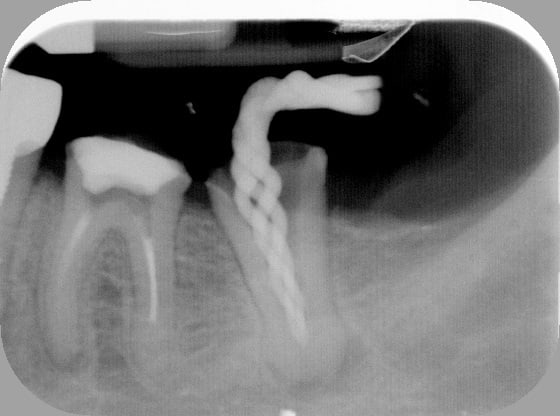

26/12/2011 à 22h01

Tout est évidemment nécrosé, et donc aucune constriction sauf étrangement en D. J'y suis donc allé au sonar électronique.

Aucun symptôme, pas de suintement, faible saignement au bout des cônes de papier dont je suis venu à bout avec 3 ou 4 sachets de 5 cônes.

Maître cône ajusté sur donnée du magnifique localisateur Joypex 5, c'est-à-dire coupé la gutta au bout pour que ça colle à la longueur électronique.

Et thermocompacteur en restant à 5 mm de la LT

Il y a l'air d'y avoir un cône en M (j'aimerais croire que ce n'est que de la pâte), peut-être aurais-je dû donner un coup de finger spreader avant pour bien écraser et mouler le cône.

Et une compression au fouloir à amalgame de gutta sur le plancher pour compresser de la pâte sur des canaux accessoires du plancher, ici apparemment absents.

Temporisation à l'IRM.

Étrange la forme en distal de la racine distale..

Il n'y a rien d'étrange, c'est juste une résorption externe provoquée par la lipoe.